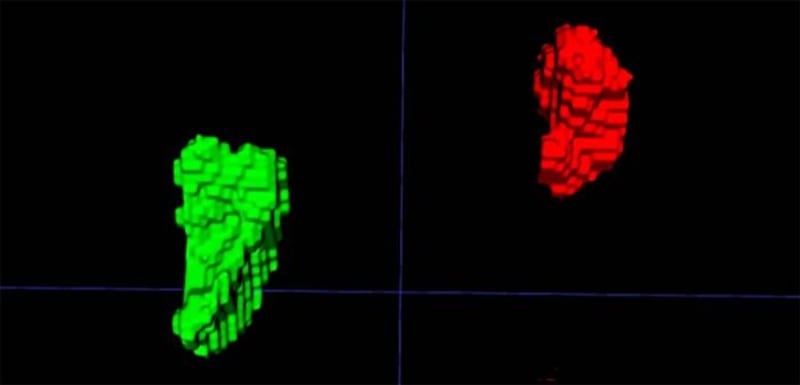

Y es que un equipo de investigadores liderado por la doctora Elena Ghotbi, del Johns Hopkins University School of Medicine, en Estados Unidos, entrenó un modelo de aprendizaje profundo para medir el volumen de las glándulas suprarrenales a partir de tomografías de tórax ya realizadas.

El indicador, llamado Índice de Volumen Suprarrenal (AVI, por sus siglas en inglés), se define como el volumen de las glándulas suprarrenales dividido por la estatura al cuadrado.

Hallaron que un AVI mayor se correlaciona con niveles más altos de cortisol, mayor carga alostática, estrés percibido elevado, y con un aumento en el riesgo futuro de insuficiencia cardiaca y mortalidad. Esto sugiere que AVI no solo refleja estrés crónico, sino que también puede predecir consecuencias graves para la salud.

Este hallazgo representa una verdadera innovación clínica: por primera vez es posible “ver” el estrés crónico acumulado en el cuerpo mediante una imagen médica habitual, en lugar de depender únicamente de cuestionarios o mediciones puntuales de cortisol.